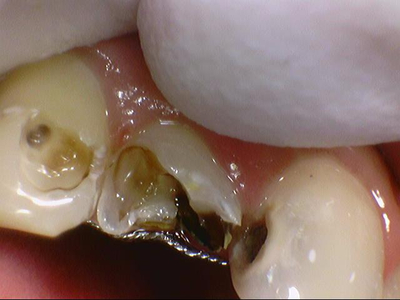

그런데 속(입천장)쪽에서 거울을 대고 봤을 때는 앞에서 봤을 때보다도 더 충치가 심각함을 알 수 있습니다.

윗니의 경우 치아 입천장쪽을 보면 충치가 아주 심한 것을 볼 수 있습니다.

어금니도 씹는면도 썩어있었지만 어금니의 옆면도 많이 썩어있었습니다.

앞니 충치 파고파고 팠는데도 아직 남아있고 치아 다 없어질 정도만 남은거 실화인가요ㅠㅠ

그래도 살리기 위해 최대한 노력하여 임플란트 없이

살렸습니다...